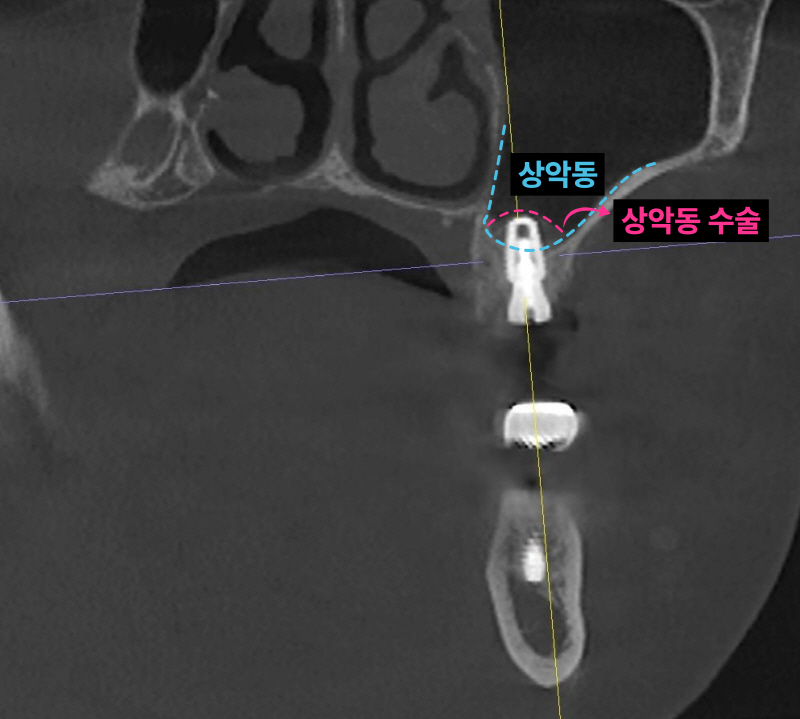

이미 신경치료된 치아 뿌리 끝에 염증이 잡혀있고 브릿지 아래로 2차충치가 크게 생겨서 임플란트로 치료 계획을 정했습니다. 임플란트 2개를 심고 치아 머리(크라운) 3개를 만듭니다. 여러 개의 임플란트를 심을 때 꼭 개수대로 임플란트를 심을 필요는 없습니다. 과거에는 발치, 상악동 수술, 임플란트를 전부 기다리며 나눠서 진행했는데 시간이 너무 오래 걸립니다. 저는 최대한 치아가 없는 기간을 단축시키기 위해서 치아를 뽑고(발치) 동시에 임플란트를 심으며 뼈가 없는 경우 상악동 수술을 동시에 진행합니다.

남아있는 잇몸뼈가 5-6mm 정도입니다. 저는 이런한 경우 덴샤버라는 특수한 기구를 이용해서 가능한 빠르면서 안아프고 쉽게 상악동 수술을 시행합니다. 항상 CT를 통해 환자분들께 정확하게 수술된 모습을 보여드립니다.